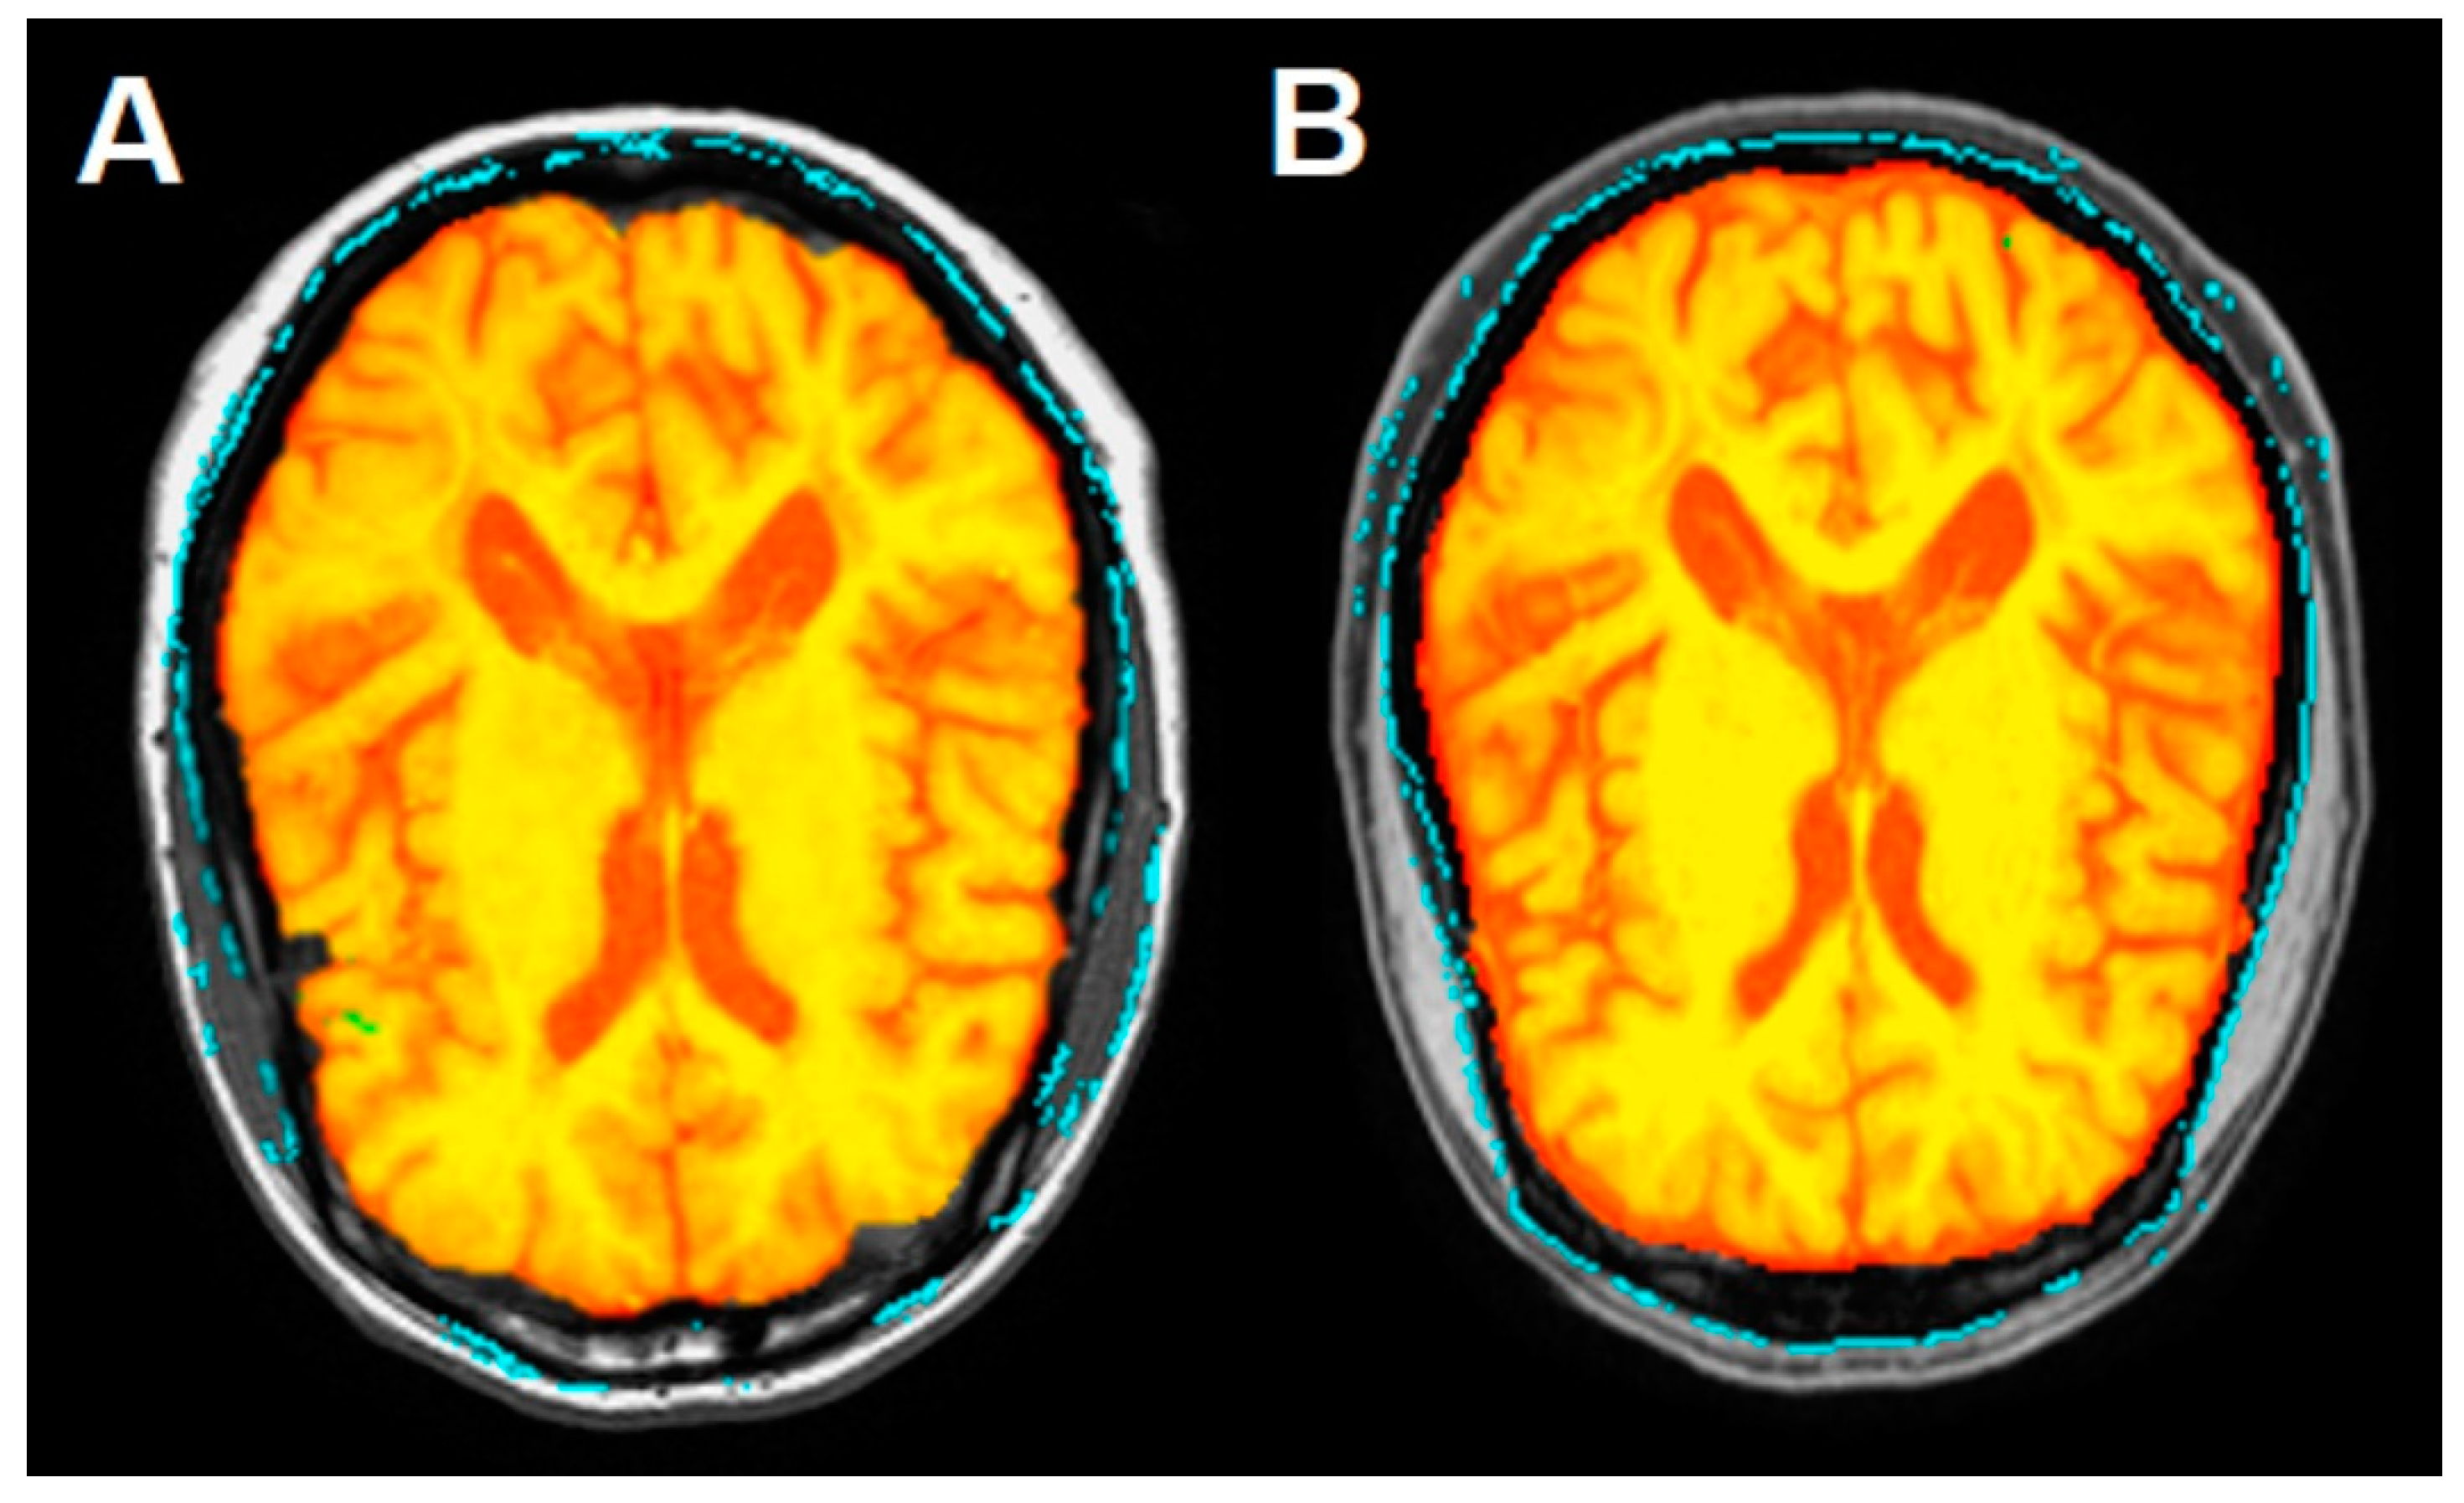

Figure 4 shows the Siena output color-coded image of the brain, while Figure 5 shows the brain parenchymal fraction in the axial image from August (Figure 5A) and September (Figure 5B), before and after DFPP procedure, respectively, with a TIV reduced by 2.14% in the latter, where subarachnoid spaces appeared to increase as expected.

Figure 5.

Pre-to-post registration axial images of the brain, before (A) and after (B) the DFPP procedure respectively, identified using the Siena tool of the FSL software. Yellow color indicates the brain parenchymal fraction, red color the ventricular system and subarachnoid spaces. Given the 2.14% reduction of total intracranial volume (TIV), note the expected prevalence of the red color in B indicating the involvement of subarachnoid spaces, with TIV = 1300.4 mL with respect to A with TIV = 1328.8 mL.

This reduction in the brain tissue volume resulted mainly from the shrinkage in grey matter and peripheral grey matter, measuring 511.2 mL and 402.9 mL respectively, according a % reduction of 1.16 and 1.14, respectively. The total cerebrospinal fluid (CSF) volume underwent a % net increase of 1.22, despite the ventricular space reduction by 1.11%. Finally, the white matter volume increased 1.14%. The patient underwent an intensive rehabilitation program with exercises focused on gait-reeducation and proprioceptive facilitation.